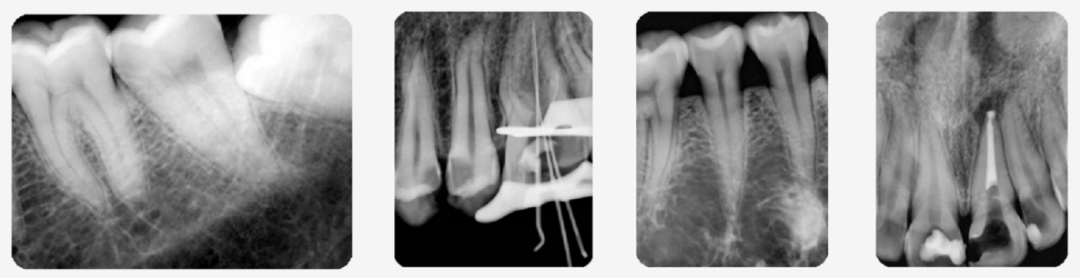

口内摄影(牙片)

高频直流高压发射器,机头内采用0.4进口小焦点球管,曝光稳定、成像清晰

口内摄影(牙片)部分采用5mA固定管电流配合高频直流发生器为设备提供稳定精准的影像。0.4进口小焦点球管,可确保清晰成像。首创分体式口内摄影(牙片)设备,可灵活选择设备安装方向,控制面板也可根据需求安装于屏蔽间的不同位置。